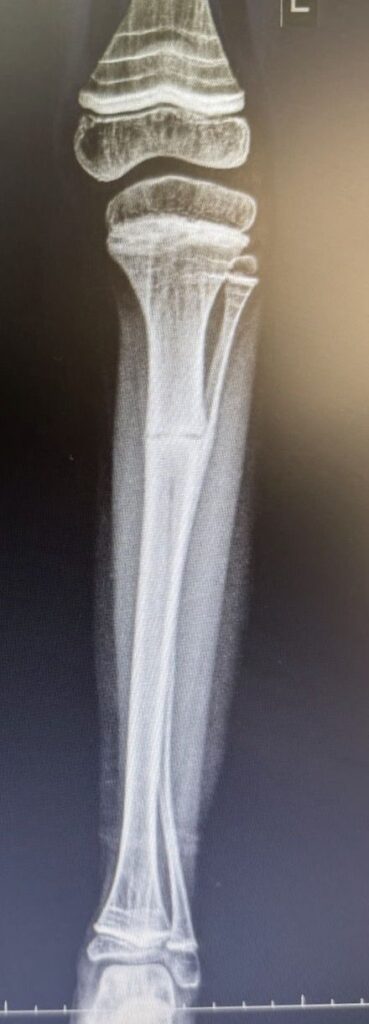

O Hospital 22 de Outubro alcançou um grande marco no último sábado (20), ao realizar a primeira cirurgia da região para correção de deformidade óssea em um paciente de 8 anos com Osteogênese Imperfeita tipo 5. O procedimento, que envolveu uma dupla osteotomia da tíbia, foi realizado pelo ortopedista e traumatologista, Dr. Guilherme Maretti Franco De Campos, e pela Dra. Michelle Cardoso, especialista em deformidades ósseas da AACD.

O paciente, que sofria de múltiplas fraturas recorrentes e apresentava uma grave deformidade na perna esquerda, foi tratado com a implantação de uma haste intramedular telescopada Fassier-Duval. Esse dispositivo, que se ajusta ao crescimento do osso, oferece suporte e estabilidade, prevenindo fraturas à medida que a criança cresce.